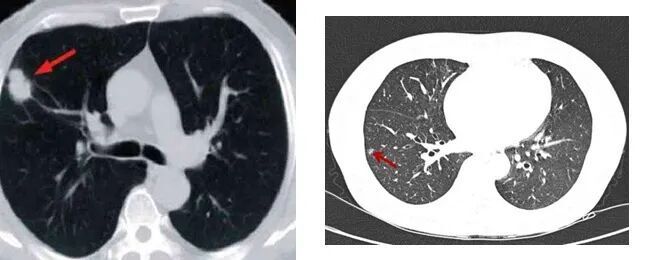

肺结节是呼吸科临床常见影像学(x线)征象,肺结节(pulmonarynodule,PN)是指肺组织内直径≤3cm、形态规则或不规则形的局灶性高密度阴影,可单发或多发,边界清晰或不清晰。

根据影像学CT上病灶密度特征表现,分为实性结节和磨玻璃结节,根据磨玻璃结节内部是否含有实性成分,把磨玻璃结节又分为纯磨玻璃结节和部分实性结节

良性肺结节密度多均匀,边缘光滑,分叶切迹不显著,病变可出现中心性、弥漫性、层状钙化特征。

恶性肺结节密度多不均匀,边缘模糊,多出现毛刺征分叶征空泡征血管集束征胸膜凹陷征等恶性征象。